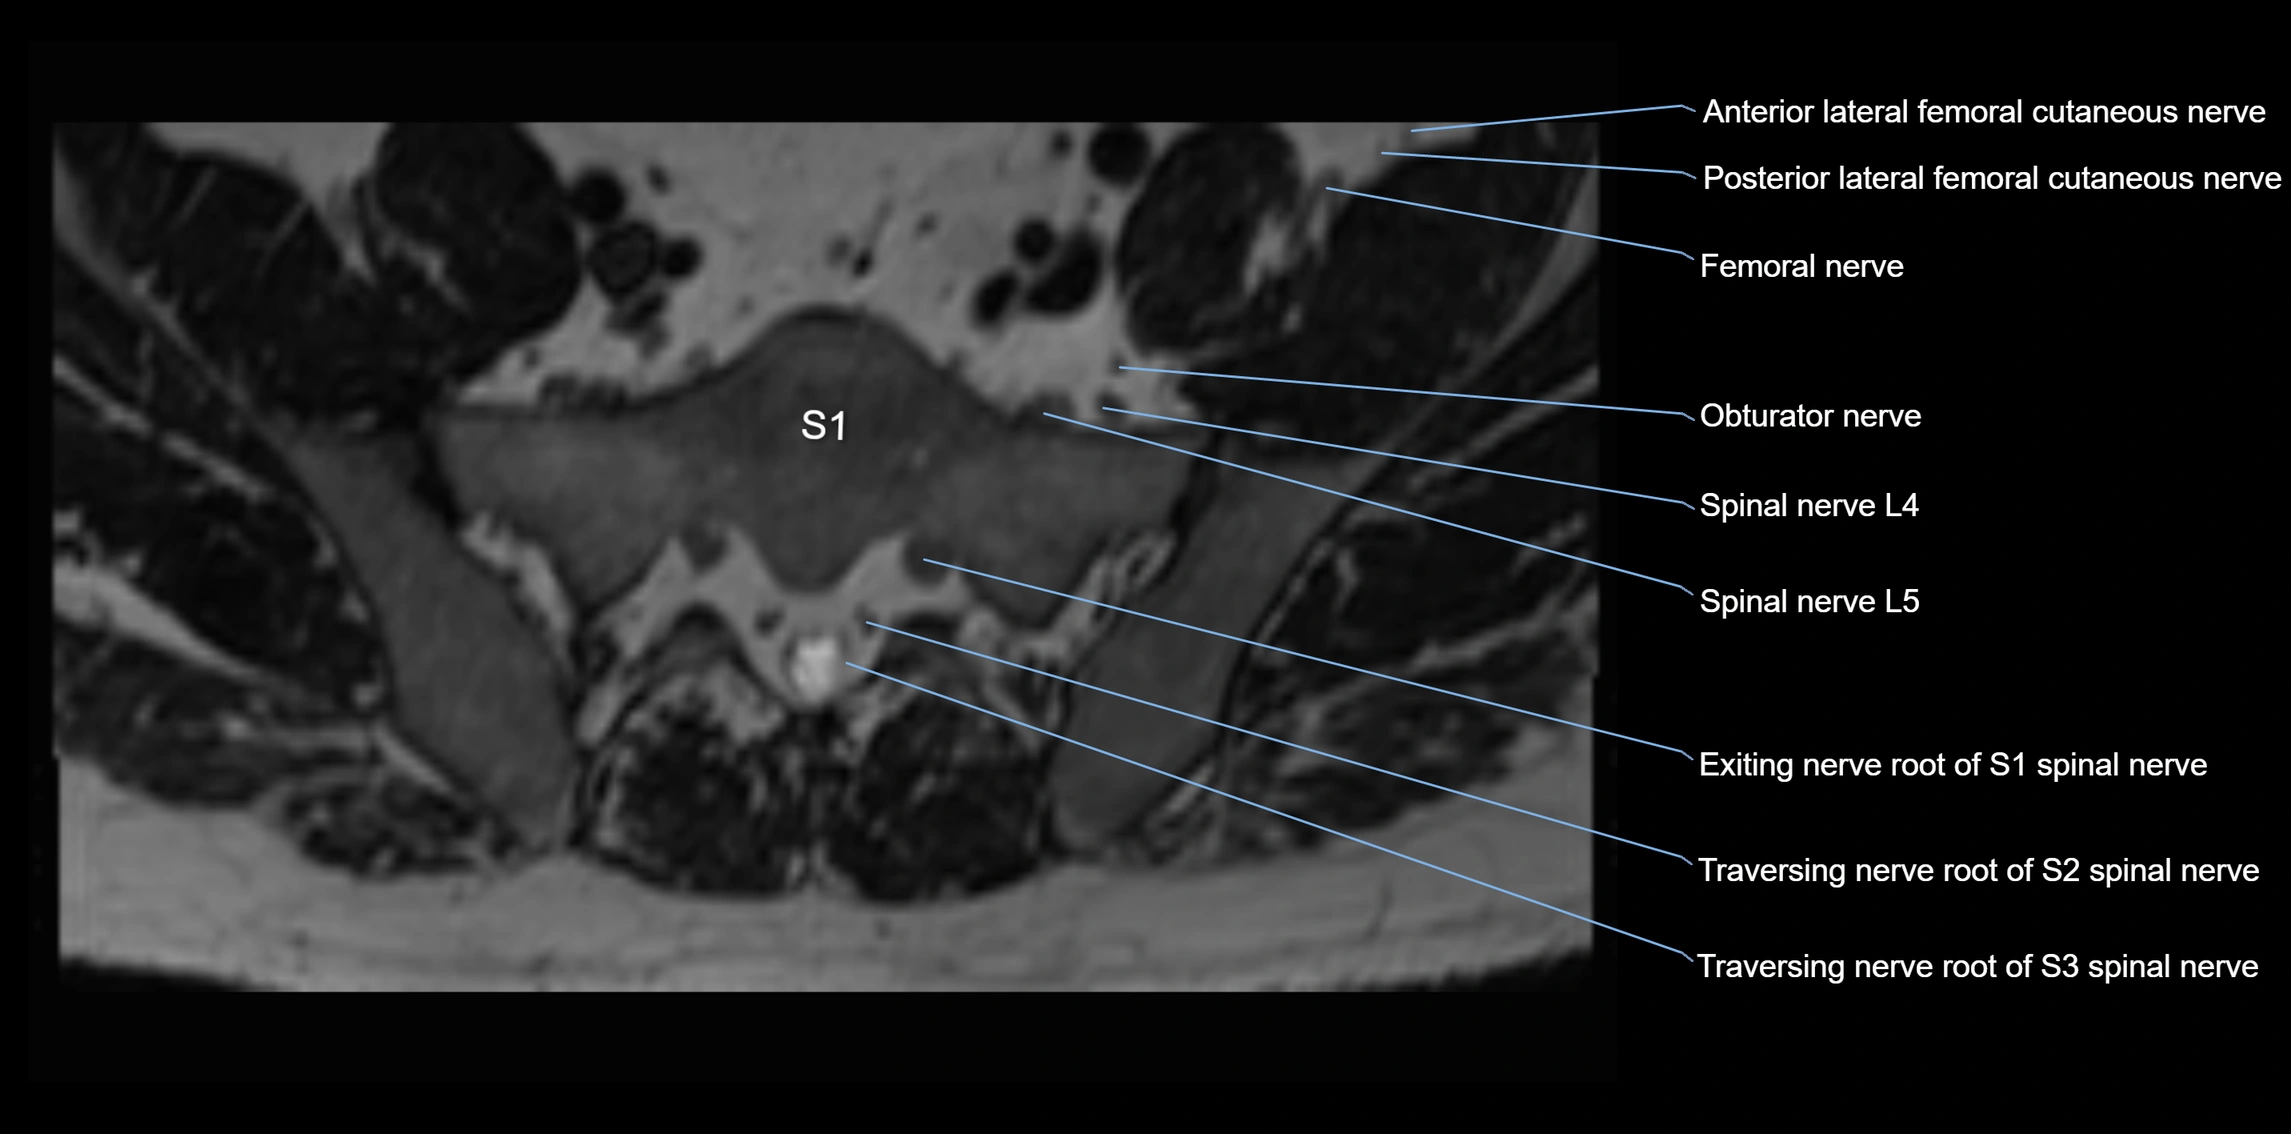

MRI image

image